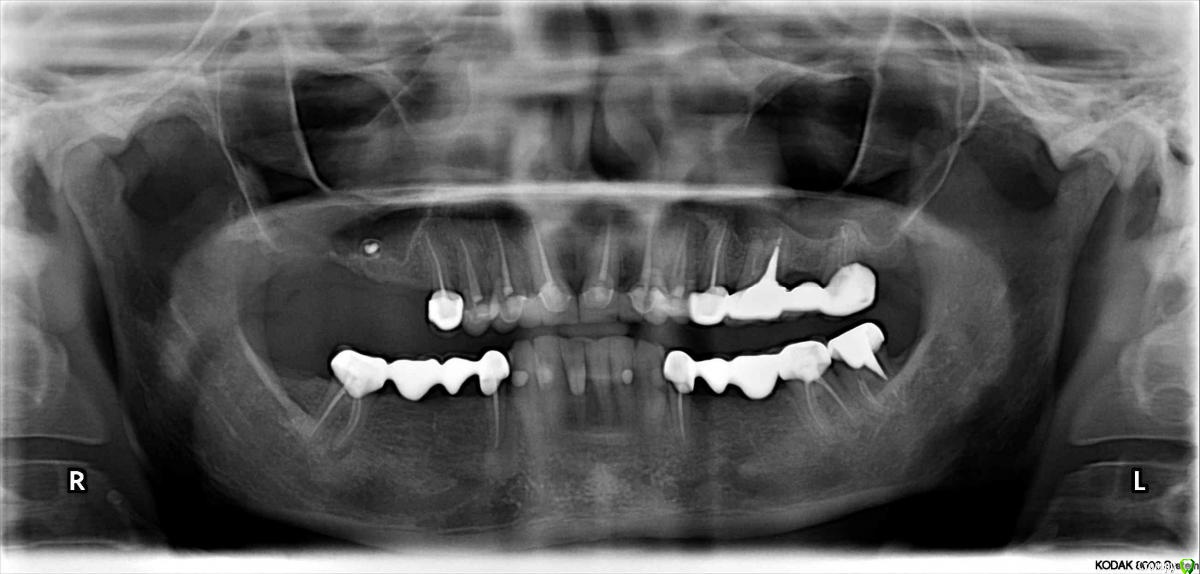

lazzal Опубликовано 29 октября, 2015 Поделиться Опубликовано 29 октября, 2015 (изменено) Уважаемые ортопеды, дайте пожалуйста совет и свои рекомендации. в 2012 г была установлена конструкция на передние верхние зубы из безметалловой керамики. 2 мини моста резец-клык справа и слева. устанавливались на свои абсолютно здоровые зубы, предварительно депульпированные, так сделать предложил врач, чтоб была типа "голливудская улыбка". у меня от природы отсутствовали двойки с обоих сторон, правда зазор был не большой, но все равно смотрелось не очень, клыки сразу бросались в глаза. так вот, врач мне сказал, что конструкция прослужит 20 лет, а у меня через 2,5 года начались проблемы. начали чернеть кромки вдоль конструкции с внутренней стороны. терапевт диагностировал кариес. ортопед сказал снимать не надо, можно их изнутри немного сточить, пролечить кариес и запломбировать. так и сделала. но пломбы теперь вылетают каждые 3-4 месяца. врач который лечит, сделал снимки и сказал, что там с правой стороны между резцом и клыком гниет корень и надо конструкцию снимать, а то потеряем корень. мой ортопед же говорит, что все нормально - пусть стоят, надо лучше пломбировать. снимать я сама не хочу конечно. но корень дороже. кто из них прав и что мне делать? еще сложность в том, что конструкция похоже крепится на какой-то супер клей и просто так ее сбить или спилить не получится (проговорился мой ортопед). я не представляю как это все может выглядеть, стешут по самые десны и сделают вкладки? очень бы этого не хотелось, т.к. хотелось бы этот вариант оставить про запас, т.к. потом, если что случись - олько имплантация и то, если это будет возможно. Посмотрите снимки и подскажите, что можно сделать им почему такой короткий срок службы? как смог развиться кариес? Так же прилагаю и панорамный снимок, возможно вы увидите и укажете мне на еще какие-то проблемы с зубами или деснами, на которые стоит обратить внимание. С уважением и благодарностью, я. Изменено 29 октября, 2015 пользователем lazzal Ссылка на комментарий

carloss Опубликовано 29 октября, 2015 Поделиться Опубликовано 29 октября, 2015 (изменено) Не факт, что все зубы, после снятия коронок можно будет оставить, но чем скорее вы это сделаете, тем больше шансов сохранить максимальное число зубов. И в плане имплантации, и будущей эстетики, тоже важно поторопиться, чтобы не так сложно, долго и дорого, было с костью и с десной. Потемнения десны из-за проблем с краевым прилеганием(точностью коронок). В норме этого не должно быть даже спустя годы, особенно на безметалловой керамике. Но у вас есть проблемы и похуже. И похоже ваш терапевт был прав - про то, что корень сгниёт. И не на одном, а на большинстве зубов. Изменено 29 октября, 2015 пользователем carloss 2 Ссылка на комментарий

Larnary Опубликовано 29 октября, 2015 Поделиться Опубликовано 29 октября, 2015 Карлосс все сказал.Я только добавлю,что речь идет не только о мостах на переднюю группу зубов верхней челюсти,но и о мостах на нижней челюсти. Ссылка на комментарий